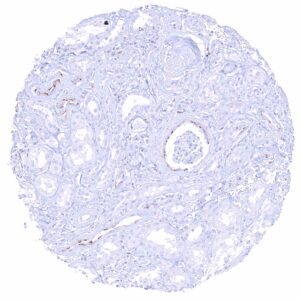

| Appendix | Distinct CD70 positivity of a fraction of lymphocytic cells, predominantly interfollicular. Epithelial cells are CD70 negative. | |

Positive control = Appendix: A distinct membranous CD70 staining should be seen in a subset of inflammatory cells (especially interfollicular).

Negative control = Appendix: CD70 staining should be absent in epithelial cells.